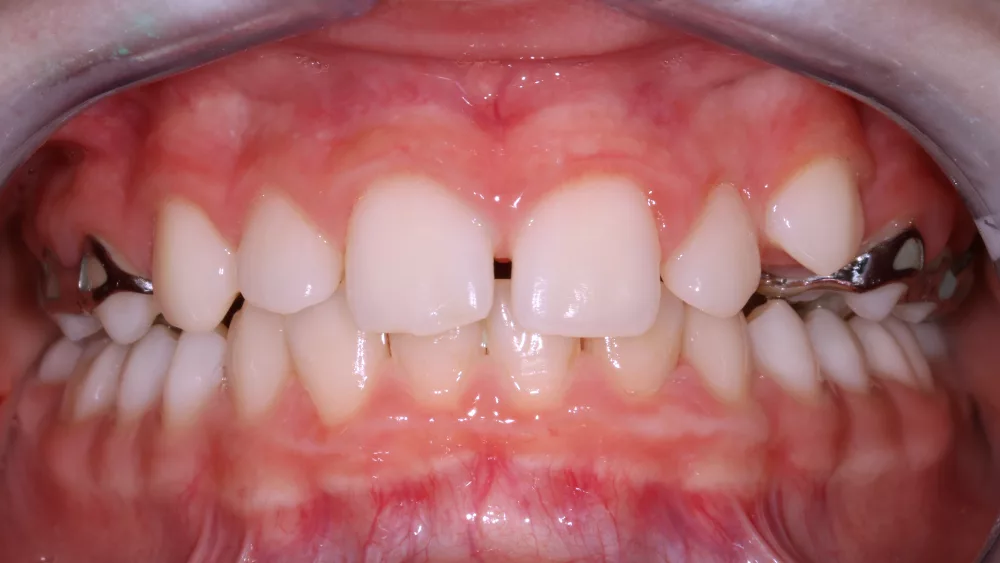

Als Beispiel für einen frühen Behandlungsbeginn wäre zum Beispiel die Behandlung eines schmalen Oberkiefers, eines Kreuzbisses oder die Behandlung eines inkompetenten Lippenschlusses zu nennen.

Die Entscheidung für eine Zahnspange bei Kindern wird häufig von ästhetischen Überlegungen begleitet. Schiefe Zähne oder sichtbare Lücken sind für Eltern und Kinder oft ein Anlass, frühzeitig über eine kieferorthopädische Behandlung nachzudenken. Aus medizinischer Sicht steht jedoch nicht das äußere Erscheinungsbild, sondern die Funktion im Vordergrund.

Eine Zahnspange ist dann medizinisch sinnvoll, wenn Fehlstellungen den Biss, die Kaufunktion oder die Entwicklung des Kiefers beeinträchtigen. Unbehandelte Fehlstellungen können langfristig zu Problemen beim Kauen, Sprechen oder zu einer erhöhten Abnutzung der Zähne führen. In solchen Fällen ist eine frühzeitige kieferorthopädische Abklärung wichtig, um den optimalen Behandlungszeitpunkt festzulegen.